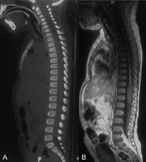

Thoracic spinal cord injury without radiologic abnormality in a pediatric patient case report

Juan Iaconis Campbell and others

Journal of Surgical Case Reports, Volume 2018, Issue 10, October 2018, rjy250, https://doi.org/10.1093/jscr/rjy250